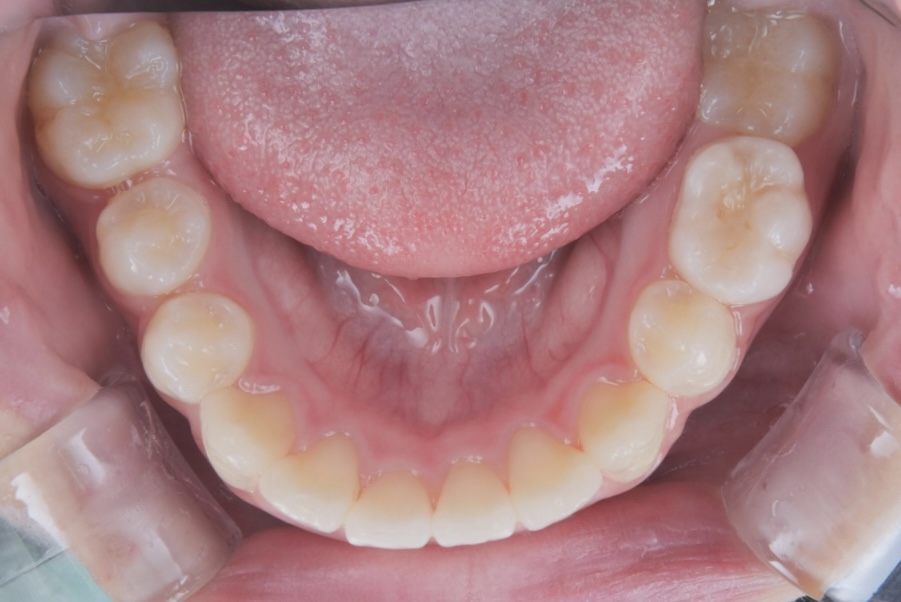

Before 2

After 2